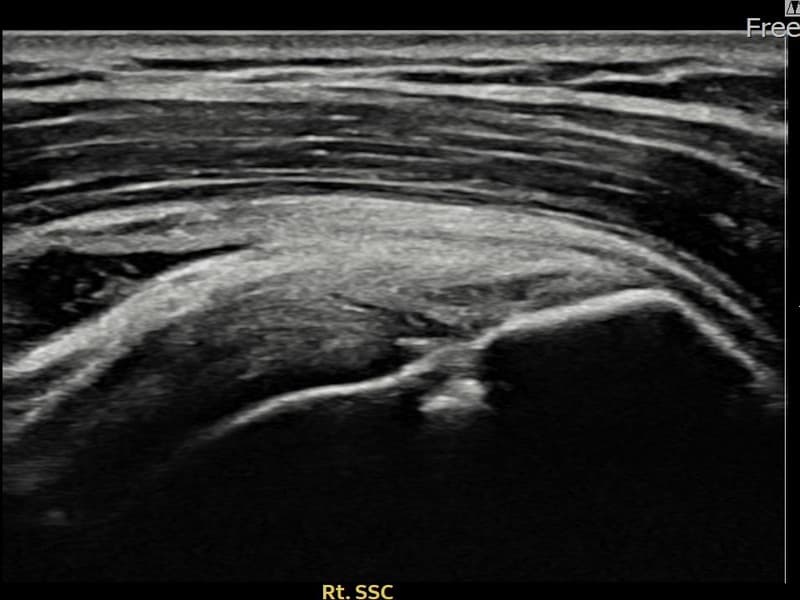

超声确认右侧 冈下肌腱 关节面侧部分撕裂(7mm × 3mm (肌腱厚度约32%缺损))。缩小缝合术后肌腱连续性恢复,患者回归正常生活。

术前超声确认右侧 冈下肌腱 关节面侧部分撕裂,右侧冈下肌腱回声不连续伴肌腱缺损(7mm × 3mm (肌腱厚度约32%缺损))。术后超声显示撕裂部位充满再生组织,肌腱连续性恢复,回声模式正常化。

该患者持续肩痛。详细超声检查确认右侧 冈下肌腱 关节面侧部分撕裂(缺损:7mm × 3mm (肌腱厚度约32%缺损))。在超声引导下实施非手术缩小缝合术。术后佩戴支具约4-6周,随后进行分阶段康复锻炼。随访超声确认肌腱连续性恢复、结构稳定,患者顺利回归日常生活。